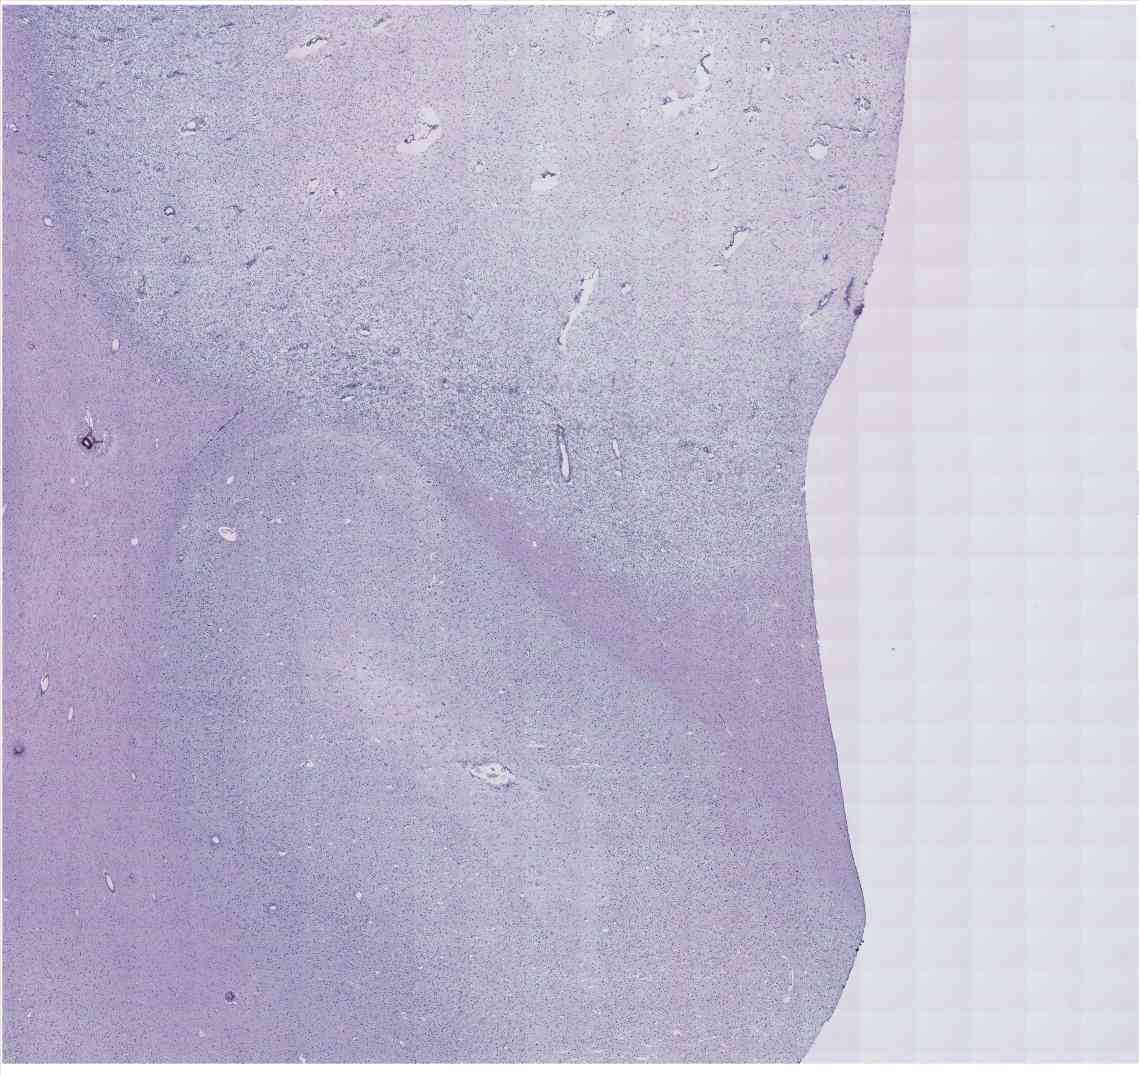

Chip 026 Well D2